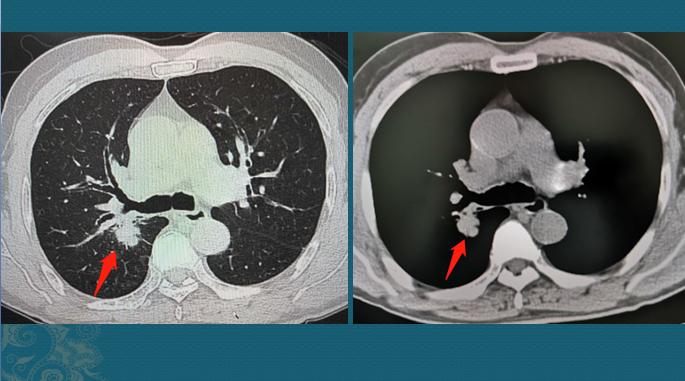

这位病人后来做了4个周期化疗(吉西他滨+奈他铂),效果非常好,在第三周期化疗后做了一次CT复查,肿瘤显著缩小:

事实上,晚期肺癌经过综合治疗,生存5年以上的病人越来越多了,并且能保证很好的生活质量。无论选择哪种治疗方式,都可以向主治医生咨询大致的费用,预期可能达到的效果等,量力而行。在能力允许的前提下,既避免人财两空,也不轻易放手,毕竟家人的生命只有一次。